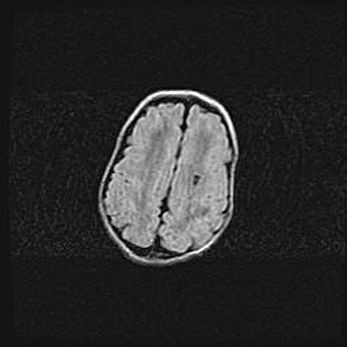

Сообщающаяся гидроцефалия. Кистозная энцефаломаляция головного мозга.

Возраст: 3 месяца 4 дня

Вес: 3100 г

Пол: женский

Окружность головы: 34 см

Срок гестации: 31 неделя

Кистозная энцефаломаляция головного мозга - одна из форм поражения головного мозга в детском возрасте. Характеризуется возникновением множественных и распространённых кист в коре, белом веществе и подкорковых образованиях головного мозга у плодов, новорождённых и детей раннего возраста. Развитие кистозной энцефаломаляции связано с внутриутробной асфиксией и гипотонией, родовой травмой, тромбозом синусов, пороками развития сосудов, инфекциями, сепсисом и другими причинами. Наиболее значимые инфекционные агенты: вирусы простого герпеса, цитомегалии, краснухи, токсоплазмы, энтеробактерии, золотистый стафилококк и другие.